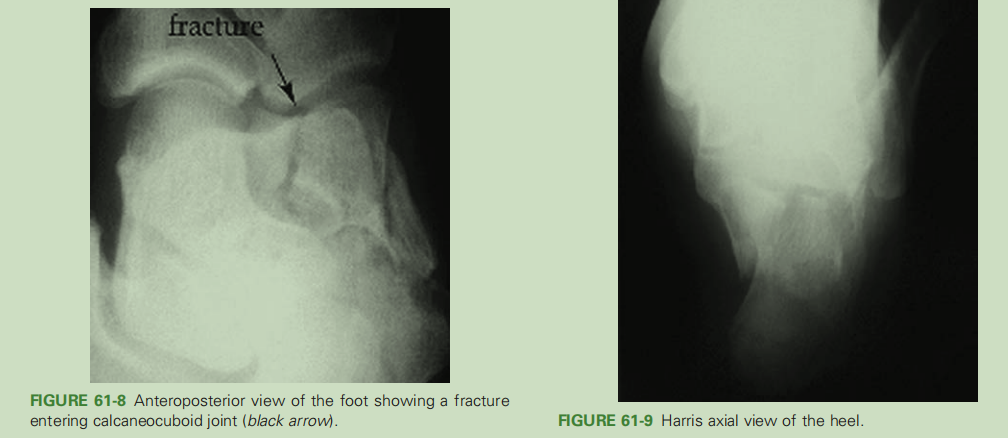

足正位X线片显示跟骰关节骨折(体现了足正位X线片的意义)